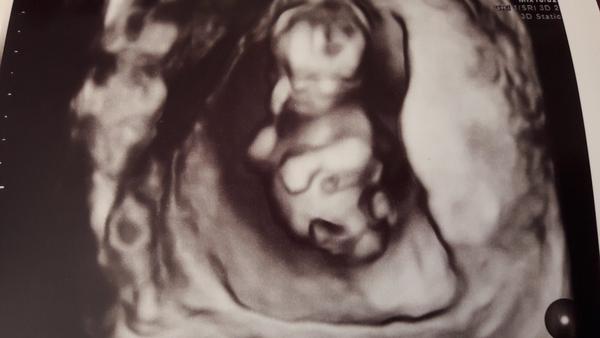

Ahojte dievcata 🙂. Pridavam sa k vam 🙂. Dnes sme boli s manzelom na prvotrimestrialny skrinig. Vsetko vyzera byt ok, cakame na vysledky krvi. Male sa nechcelo velmi ukazat a stale sa mrvilo tak na fotkach vyzera ako maly mimozemstan :D, ale na sone bolo nadherne 😍

@sasenka04 ahoj tak vy ste uz aky krasny, to je foto z 3D?